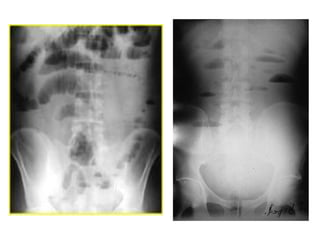

• Estrangulación

• Pocos niveles hidroaéreos

• En radiografías seriadas no cambia de localización

• Imagen en grano de café: Obstrucción incompleta en

asa cerrada

• Neumoperitoneo perforación

• Líquido libre intraperitoneal

– Se acumula en pelvis (signo de las orejas de

perro) y asciende por gotieras paracólicas

(signo del flanco)

– Imagen homogénea de densidad agua

• Íleo biliar

– Aerobilia

– Puede verse el cálculo si contiene sales

cálcicas

• Íleo paralítico

– Dilatación de intestino grueso, delgado e

incluso estómago

– Puede haber dilatación segmentaria (asa

centinela) en intestino cercano a zona

inflamatoria

– Escasos niveles hidroaéreos